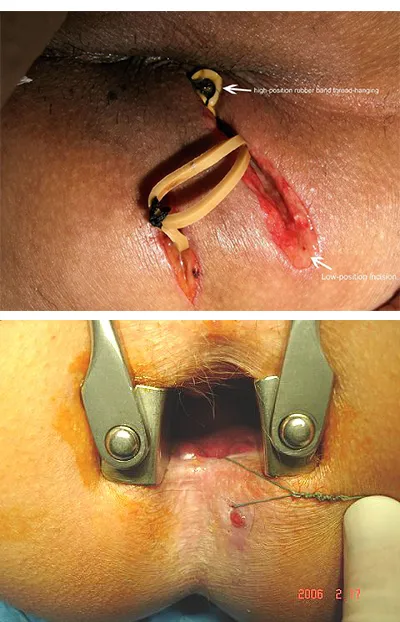

| 5. تکنیک Seton | قرار دادن نخ جراحی برای درمان فیستول | کنترل عفونت، کاهش بازگشت فیستول | مدت زمان درمان طولانی، ممکن است مناسب همه نوع فیستولی نباشد |

انواع فیستول مقعد

- فیستول سطحی کانالی کم عمق در پوست اطراف مقعد است که وارد عضلات اسفنکتر نمی شود

- فیستول زیر مخاطی کانالی است که زیر مخاط کانال مقعد قرار دارد و به سطح پوست راه پیدا می کند

- فیستول بین اسفنکتری بین عضلات اسفنکتر داخلی و خارجی ایجاد می شود و از میان این دو عبور می کند

- فیستول ترانس اسفنکتری از میان عضله اسفنکتر خارجی عبور می کند و دهانه خارجی آن روی پوست اطراف مقعد باز می شود

- فیستول سوپرا اسفنکتری از بالای عضله اسفنکتر خارجی عبور می کند و سپس به سمت پایین به پوست اطراف مقعد می رسد

- فیستول اکسترا اسفنکتری از راست روده یا روده بالاتر آغاز می شود و بدون عبور مستقیم از اسفنکترها به پوست اطراف مقعد راه پیدا می کند

- فیستول نعل اسبی فیستولی است که به شکل قوس در اطراف مقعد و در دو طرف کسترش پیدا می کند و دهانه متعدد دارد